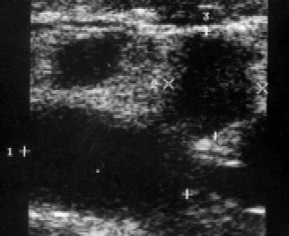

A beteg, 53 éves, fellebbezést nyújtott be a radiológiai klinikán panaszok megjelent három héttel ezelőtt, egy csomót a jobb kulcscsont feletti régióban. Nézve a jobb oldali supraclavicularis tapintható szilárd konzisztenciájú mozgásszegény képződése körülbelül 3 cm átmérőjű, feltételezett tumor folyamat. Held tűbiopszia citológia. Az így kapott anyagot talált sejtek mirigyes rák. Ismételt klinikai vizsgálat kimutatta, csomóponti oktatás a jobb pajzsmirigy lebeny. A feltételezett diagnózis „pajzsmirigyrák áttétekkel a supraclavicularis nyirokcsomó” célja, hogy a beteg ultrahangvizsgálat a pajzsmirigy. Amikor ultrahang pajzsmirigy nem nőtt mérete - 15 ml térfogatú a vozrostnoy sebességgel, hogy 19 ml. A kontúrok a prosztata sima, szimmetrikus részesedése. A háttérben egy homogén, finomszemcsés, átlagos parenchimális echogenicitása a jobb lebeny a nyúlvány határozza meg a folyadék, amely a kialakulását 15x10 mm. Képződése a belső kontúrja a láthatóvá izoehogennoe (viszonyítva a környező parenchyma) szilárd zárványok (ábra. 1).

Ábra. 1. A bal lebeny a pajzsmirigy térhatású obrazovniem.